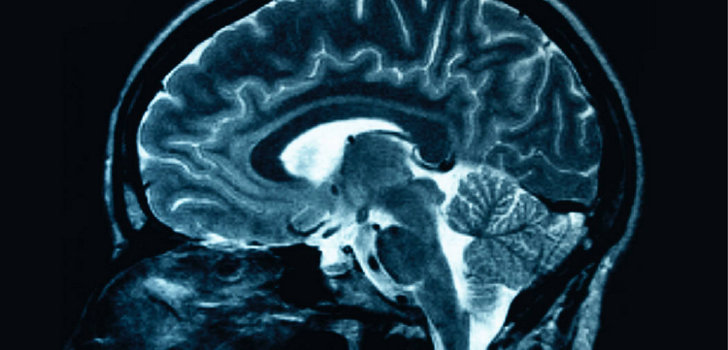

L’autismo colpisce diverse parti del cervello di uomini e donne. Lo rivela una nuova ricerca pubblicata sulla rivista Brain condotta dall’Autism Research Centre dell’Universita’ di Cambridge. Mirror-Neuron-Malfunctions-May-Underlie-AutismI risultati mostrano che l’anatomia del cervello delle persone autistiche dipende sostanzialmente dal sesso dell’individuo affetto dal disturbo: le aree cerebrali che appaiono atipiche nelle donne autistiche adulte subiscono, da una prospettiva neuroanatomica, una “mascolinizzazione”. “Cio’ potrebbe essere provocato da fattori fisiologici che inducono il dimorfismo sessuale, come gli ormoni sessuali prenatali o meccanismi genetici correlati al sesso”, hanno detto i ricercatori. L’autismo colpisce circa l’un per cento della popolazione generale ed e’ piu’ frequente nei maschi. La maggior parte degli studi e’ dunque concentrata in maniera predominante sui maschi.

“I nostri risultati suggeriscono che non dobbiamo ciecamente dare per scontato che cio’ che osserviamo nei maschi valga anche per le femmine – ha spiegato Lai Meng-Chuan, autore dello studio – anche se l’autismo si manifesta in modi diversi, la classificazione in sottogruppi per genere potrebbe fornirci una migliore comprensione della condizione”.